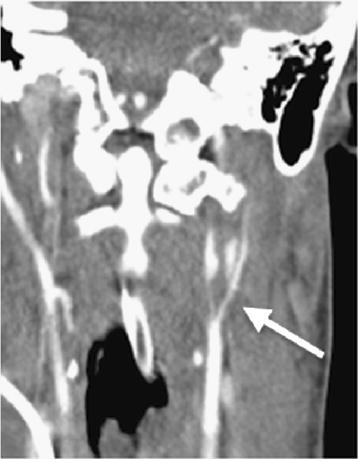

We report on a 28-year-old female major trauma patient (injury severity score, ISS 50) who was involved in a motor vehicle accident. She was primarily transferred to a level II trauma center. After initial assessment and operative management, an anisocoria was diagnosed on the intensive care unit. Subsequent CT angiography and extracranial duplex sonography revealed a bilateral internal carotid artery dissection. The patient was transferred to our level I trauma center where conservative treatment with high-dose heparin therapy was started at day two after trauma. Outcome after 6 months was very good.

我们报告一名28岁女性严重创伤患者(损伤严重度评分,ISS 50),她遭遇了机动车事故。她最初被转至二级创伤中心。经过初步评估和手术处理后,在重症监护病房诊断出瞳孔不等大。随后的CT血管造影和颅外双功超声检查显示双侧颈内动脉夹层。患者被转至我们的一级创伤中心,于创伤后第二天开始采用大剂量肝素治疗进行保守治疗。6个月后的结果非常好。